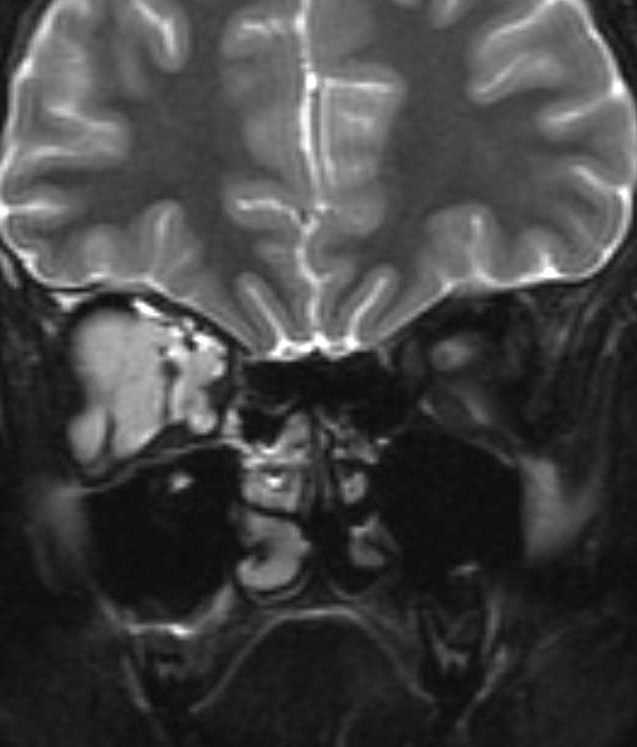

MRI of large LM cyst (top), catheter passing through lower lid (left), cystogram (right).